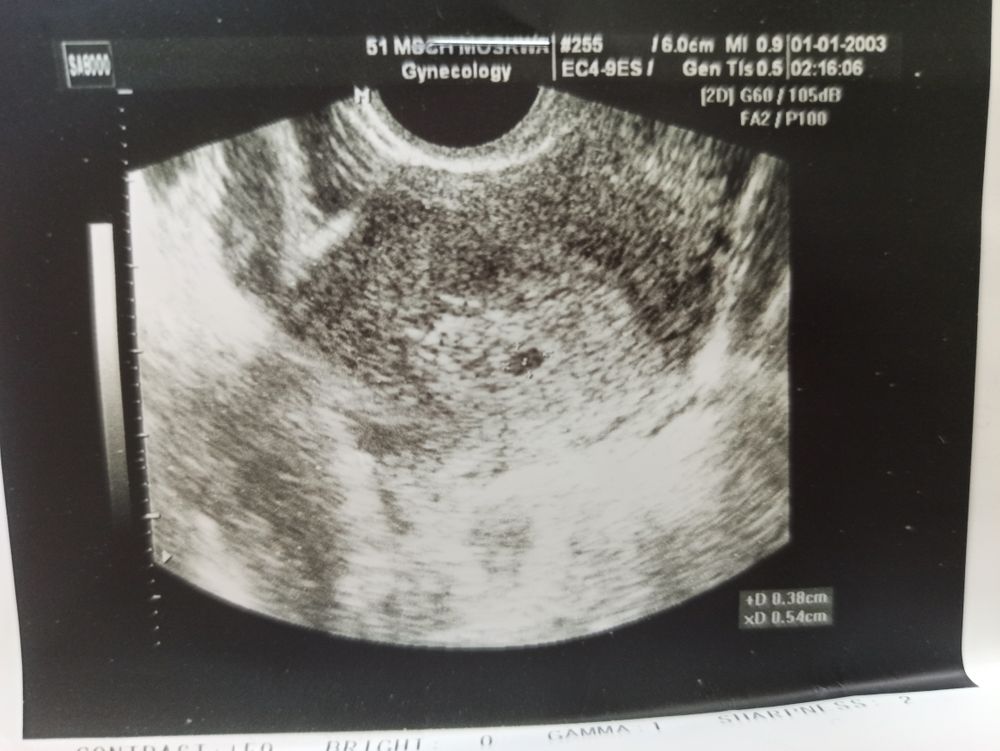

К сожалению врятли появится,у вас скорее всего анэмбриония,ее ставят уже при пя 15 мм и отсутствие жм в нем или с жм но при пя в 25 мм и без эмбриона,у меня была перед этой беременностью анэмбриония,в 6+5 пя было 20 мм и был жм 5 мм,который давал маленькую надежду, повторное УЗИ через 2 дня в 7 недель пя 22,6 мм и жм 5,3 и пусто и контрольное ещё через 3 дня в 7+3 пя 26 мм,жм 6,3 и пусто,на этом закончилась моя беременность медикаментозным абортом((( увы ... у вас жм нет в таком пя СВД его уже = 21+27/2 =24 мм и шансов практически нет( но странно если вы пишите зачатие возможно 6 сентября,тогда это 19 дпо и срок 4+4, но ваше пя на срок 7 недель,никак не на 4-5,если только ошибка в измерениях,тогда все может быть хорошо

Да у вас точно не 21 мм,это ошибка в протоколе,все хорошо у вас и соответствует вашему сроку,зря только панику мы тут навели, естественно в таком пя ни жм ни эмбриона не будет,это совсем маленький срок

Daria, нет это была анэмбриония ( но там и срок уже 7 недель был,в нормальную беременность в пя 19 мм на сроке 6+3 был эмбрион и сб